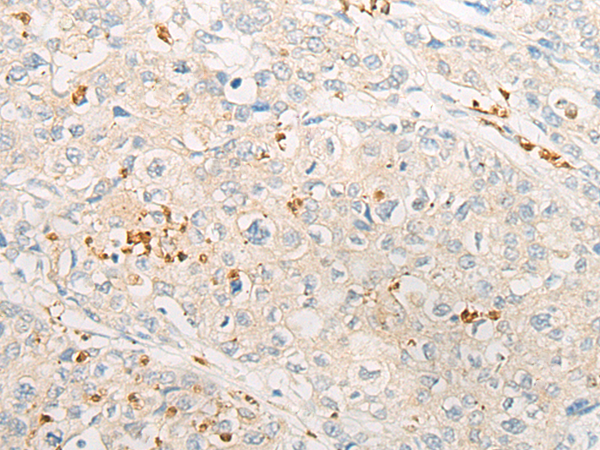

分类: 科研抗体货号: P06324别名: GRFR; GHRFR; IGHD1B应用: IHC反应种属: Human